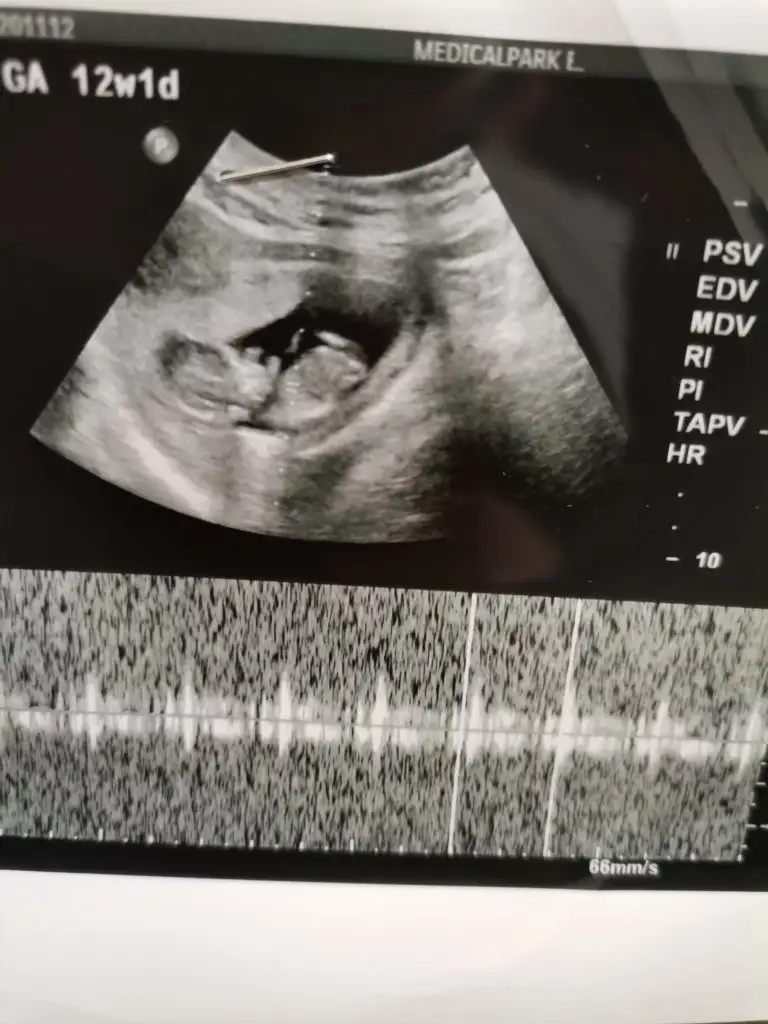

Aminnnnn. Benim de küçük bir adamım var. İnsallah bir de kızım olur. Hamileyim şuan :)

Adet olarak hesaplama da 8 haftalık ama doktor 9+3 dedi burda bakarmısınız 🙏🙏🙏🙏